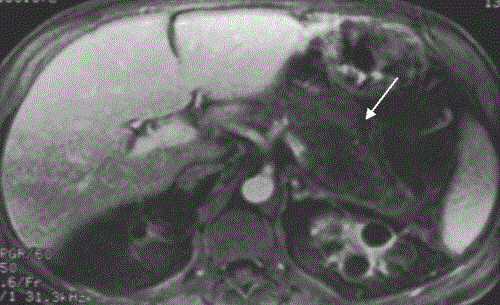

Figure 5. Axial T1w fat-sat acquisition obtained postgadolinium intravenous infusion. The entire pancreatic tail shows absent enhancement due to gland necrosis.